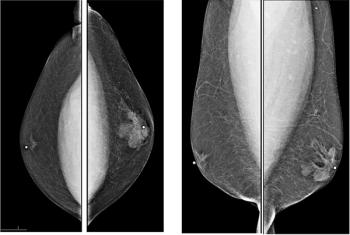

49-year-old patient presented for bilateral screening mammogram as well as bilateral screening ultrasound due to dense breast tissue.